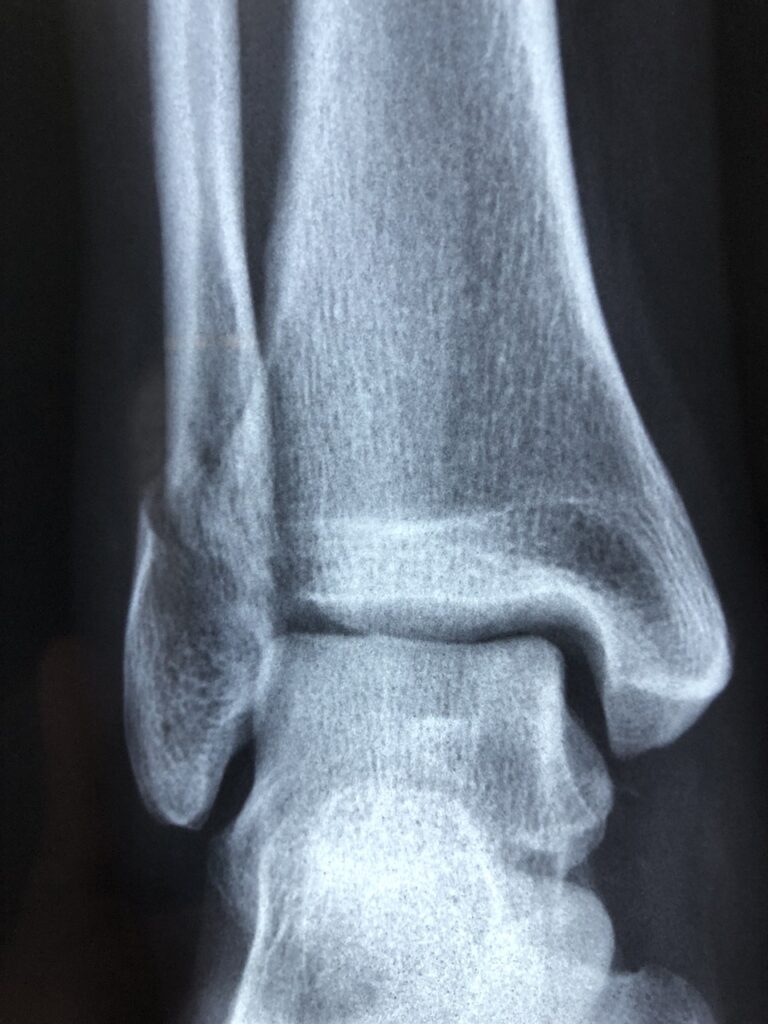

怪我の程度によっては、医師の診察を受けることが重要です。特に、痛みが強い場合や腫れがひどい場合は、専門家の意見を聞くことで適切な治療を受けることができます。